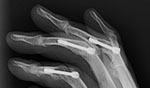

| Herbert screw |

Herbert screws |

Herbert screw |

| Note the different screw pitch on each end. From Benjamin, 1994

|

Also know as headless (recessed) fixation screws. From Taljanovic, 2005 |

There is a healing scaphoid fracture, and a fiberglass splint is in place. From Benjamin, 1994 |